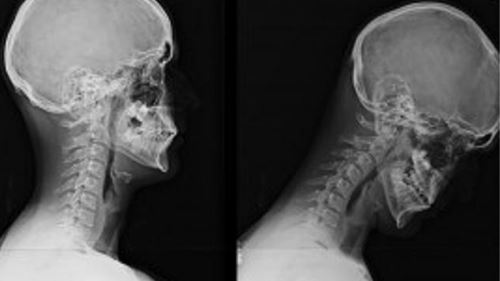

Setiap Kali Scroll Media Sosial, Leher Anda Menanggung 12kg Beban, Awas Sindrom Text Neck!